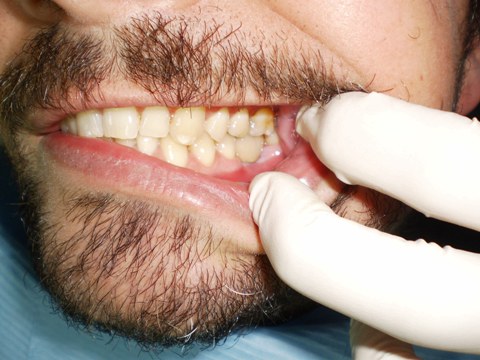

Ejemplo Implantes